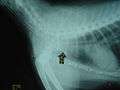

- Bottle top swallowed by a dog